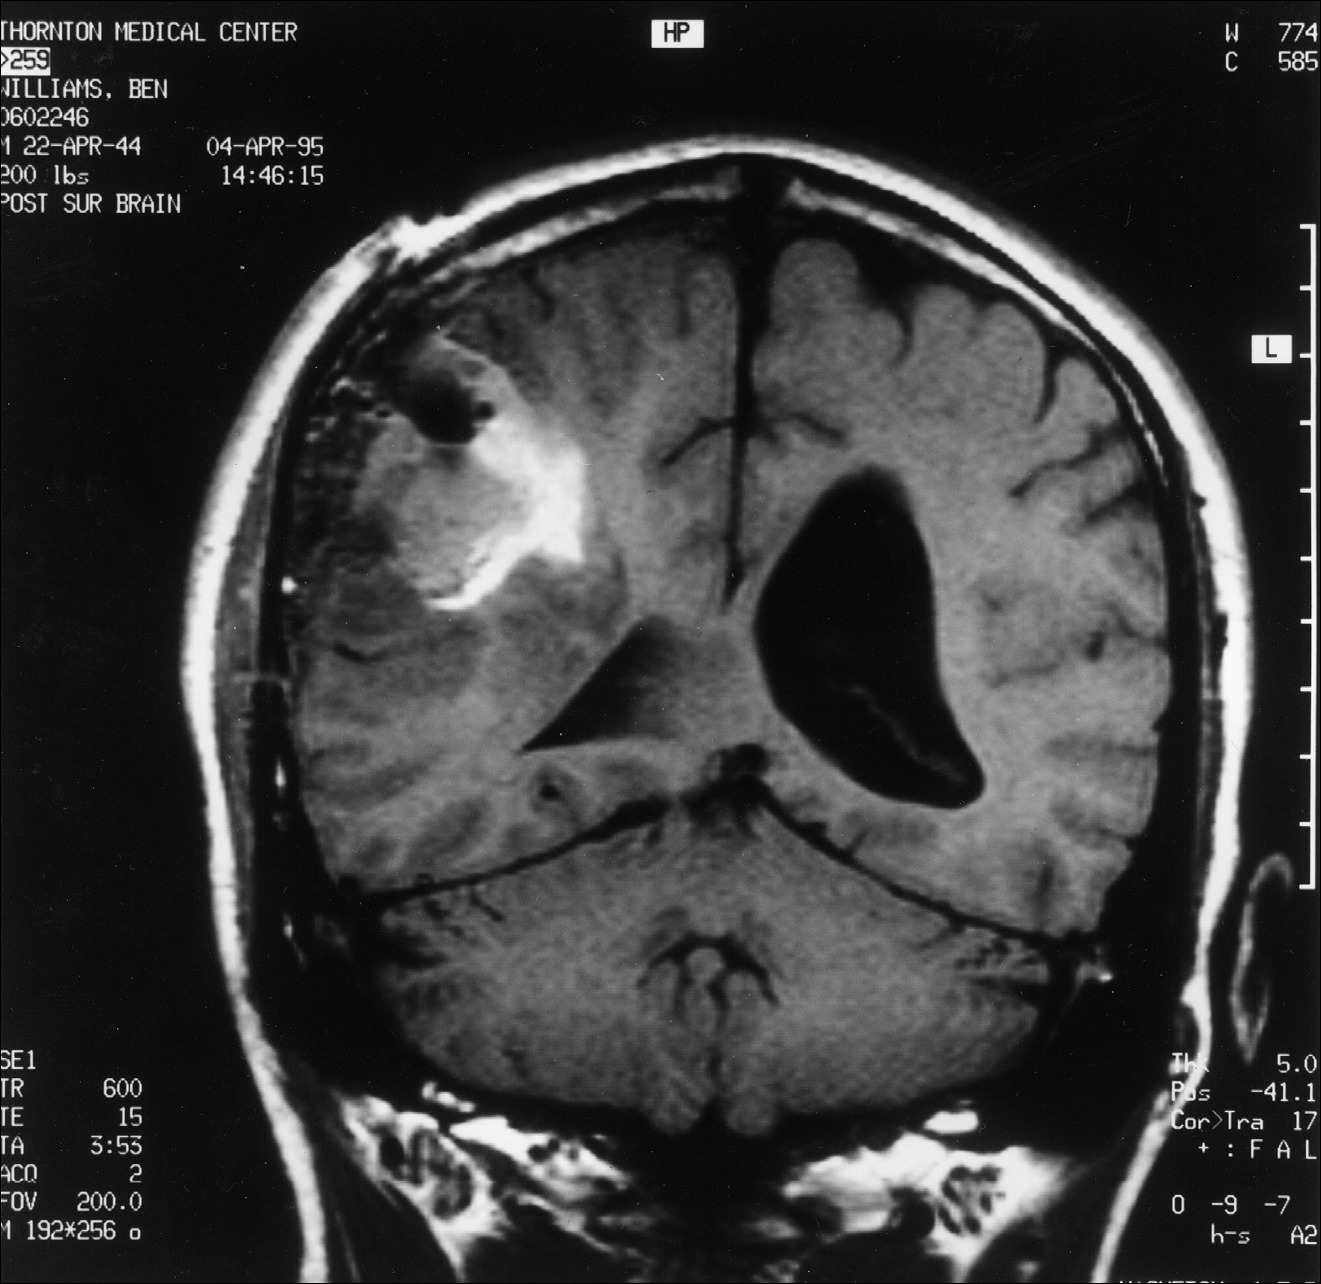

Kitą rytą su Diane susitikome su dr. Marshall aptarti MRT rezultatų. Jis paaiškino, kad stengėsi pašalinti visą matomą naviką, tačiau toli už jo ribų nėjo. Navikas buvo toks didelis, kad papildomas šalinimas būtų sukėlęs rimtų mano regėjimo problemų. Gliomos tipo smegenų navikai turi mikroskopinius ūselius, besitęsiančius du–tris centimetrus už matomų naviko ribų, todėl pašalinti visas naviko ląsteles yra nepaprastai sunku. Tik patys agresyviausi neurochirurgai sugeba pašalinti šiuos nematomus ūselius, dažnai sukeldami reikšmingą paciento funkcinį pablogėjimą. Kadangi dr. Marshall operavo konservatyviau, mano MRT parodė, kad liko nemaža naviko dalis (žr. čia ir čia). Dr. Marshall neatrodė ypač susirūpinęs dėl likusio naviko ir paminėjo, kad jo kolega dr. David Barba galėtų jį veiksmingai gydyti spindulinės terapijos implantu, vadinamu brachiterapija. Tuo metu neturėjau supratimo, apie ką jis kalba. Mano mintis užvaldė tai, kad po operacijos liko nemaža naviko dalis.

3 pav.

Pooperacinis MRT pjūvis, atliktas per smegenų vidurį tarp priekio ir galo.

4 pav.

Pooperacinis MRT pjūvis, atliktas per smegenų vidurį tarp viršaus ir apačios. Abu pjūviai rodo, kad po operacijos liko nemaža naviko dalis.